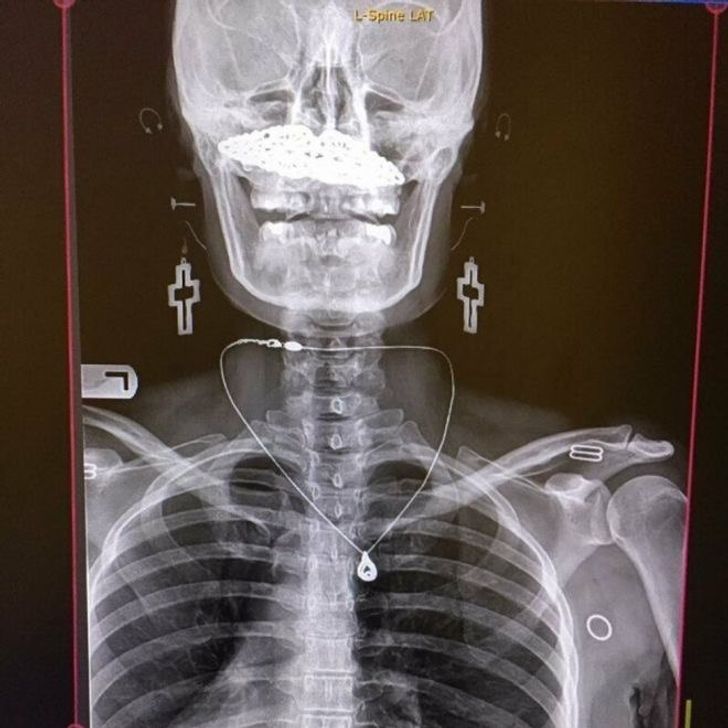

Прикраси додають рентгенівському знімку трохи чарівності

«Зробила пластику. Мій череп шимпанзе перетворився на людський»